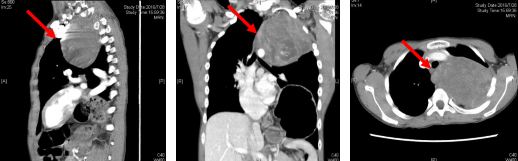

(术前MRI评估,“→”表示肿瘤所在区域)

(术前CT评估,“→”表示肿瘤所在区域)